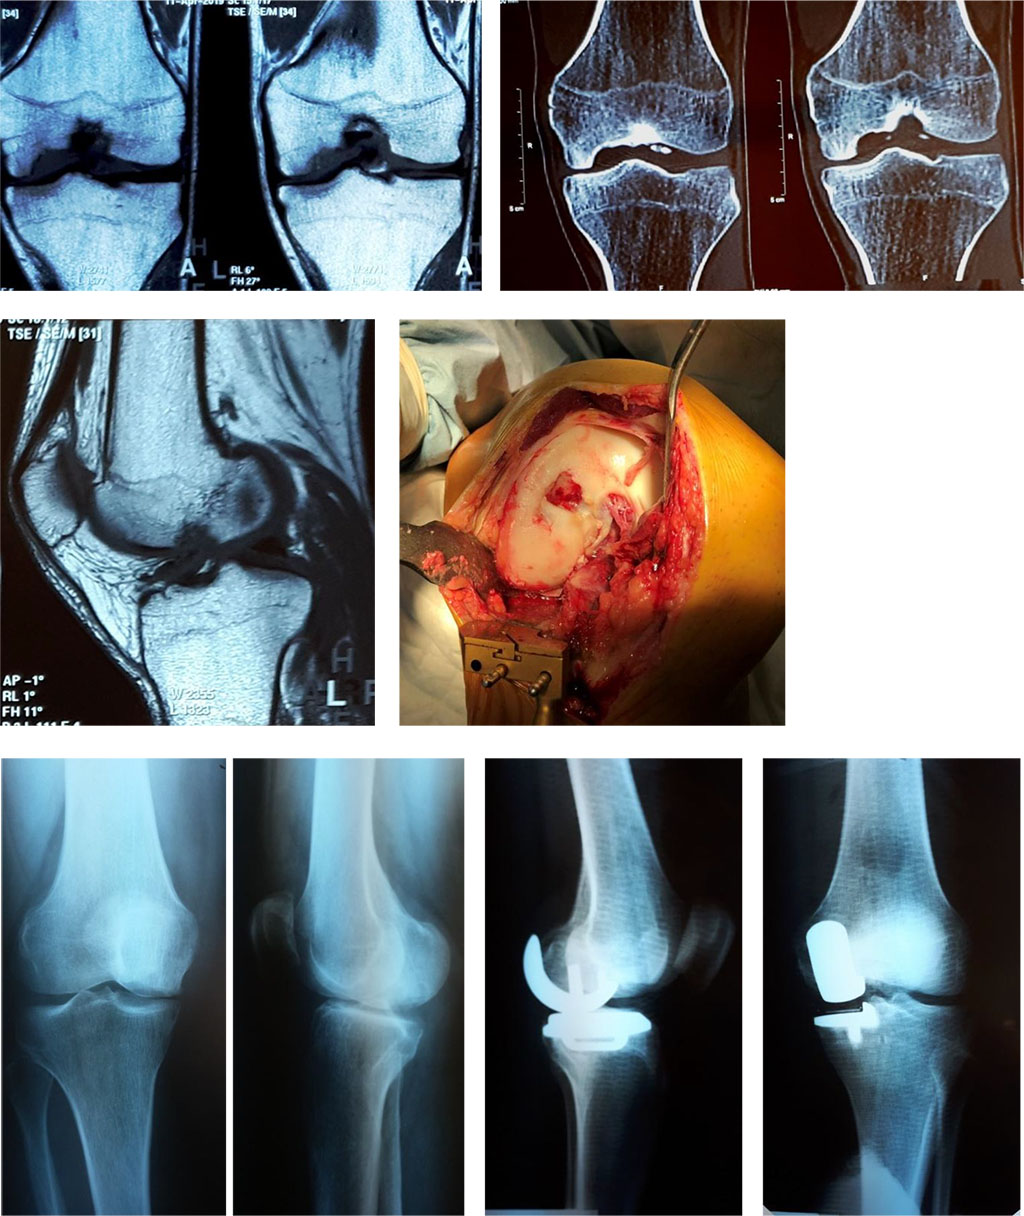

Figure 2.

Figure 2. MRI, CT of a knee, intraoperative photo of a defect of medial femoral condyle and X-ray image of the lower limb after the unicondylar arthroplasty.

Diagnosis: Deforming arthritis of the left knee, 3rd stage. Aseptic necrosis of the left femoral medial condyle; left knee contracture; pain syndrome.

The patient reports periodical pain in his left knee, its intensity increasing gradually during the six recent months, slight restriction of motions.

Treatment was the unicondylar arthroplasty of the left knee. Six months later, the patient walks without any additional support, mentions the absence of pain. Knee range of motions was 5/0/165˚. The result of treatment was excellent (KSS – 90).